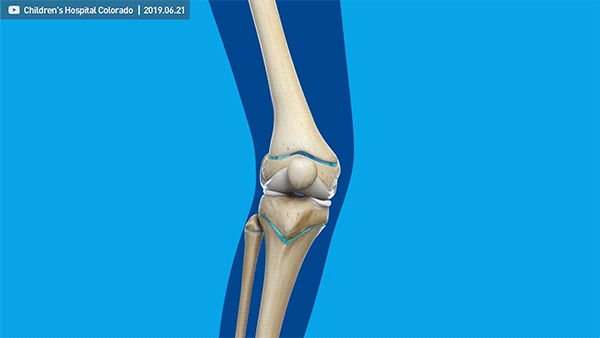

其次,可以采用半骨骺阻滞术进行治疗,也就是在畸形凸侧的生长板放置小钢板,减缓该侧生长板的生长速率,从而达到引导生长、纠正畸形的目的。

治疗结束后,取出钢板,双腿依旧能正常发育。